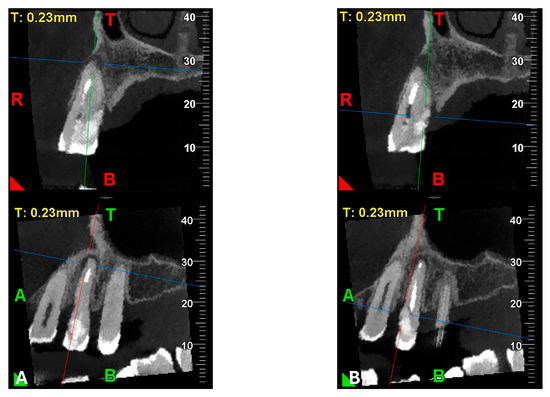

Figure 12.

Pano-rex and cross-sectional CBCT images of tooth 1.4 after six months of healing. (A,B) Sequential scrolling of tooth 1.4 after six months of healing. The colored lines crossing the images represent the orthogonal planes (axial, coronal, and sagittal) in the multiplanar reconstruction. Their correct use and orientation allow for an accurate identification of the extent of the lesions in all spatial planes and a detailed analysis of the endodontic anatomy. The green and red letters are the coordinates of the image: A: anterior, R: right, B: bottom, T: Top.

Figure 13.

Pre-treatment and 6-month follow-up healing comparison of EPL.

An intermediate follow-up CBCT scan at 6 months was performed to accurately assess the response to treatment in light of both the extent of the lesion and the patient’s systemic comorbidities (Figure 10, Figure 11, Figure 12, Figure 13 and Figure 14).

Figure 10.